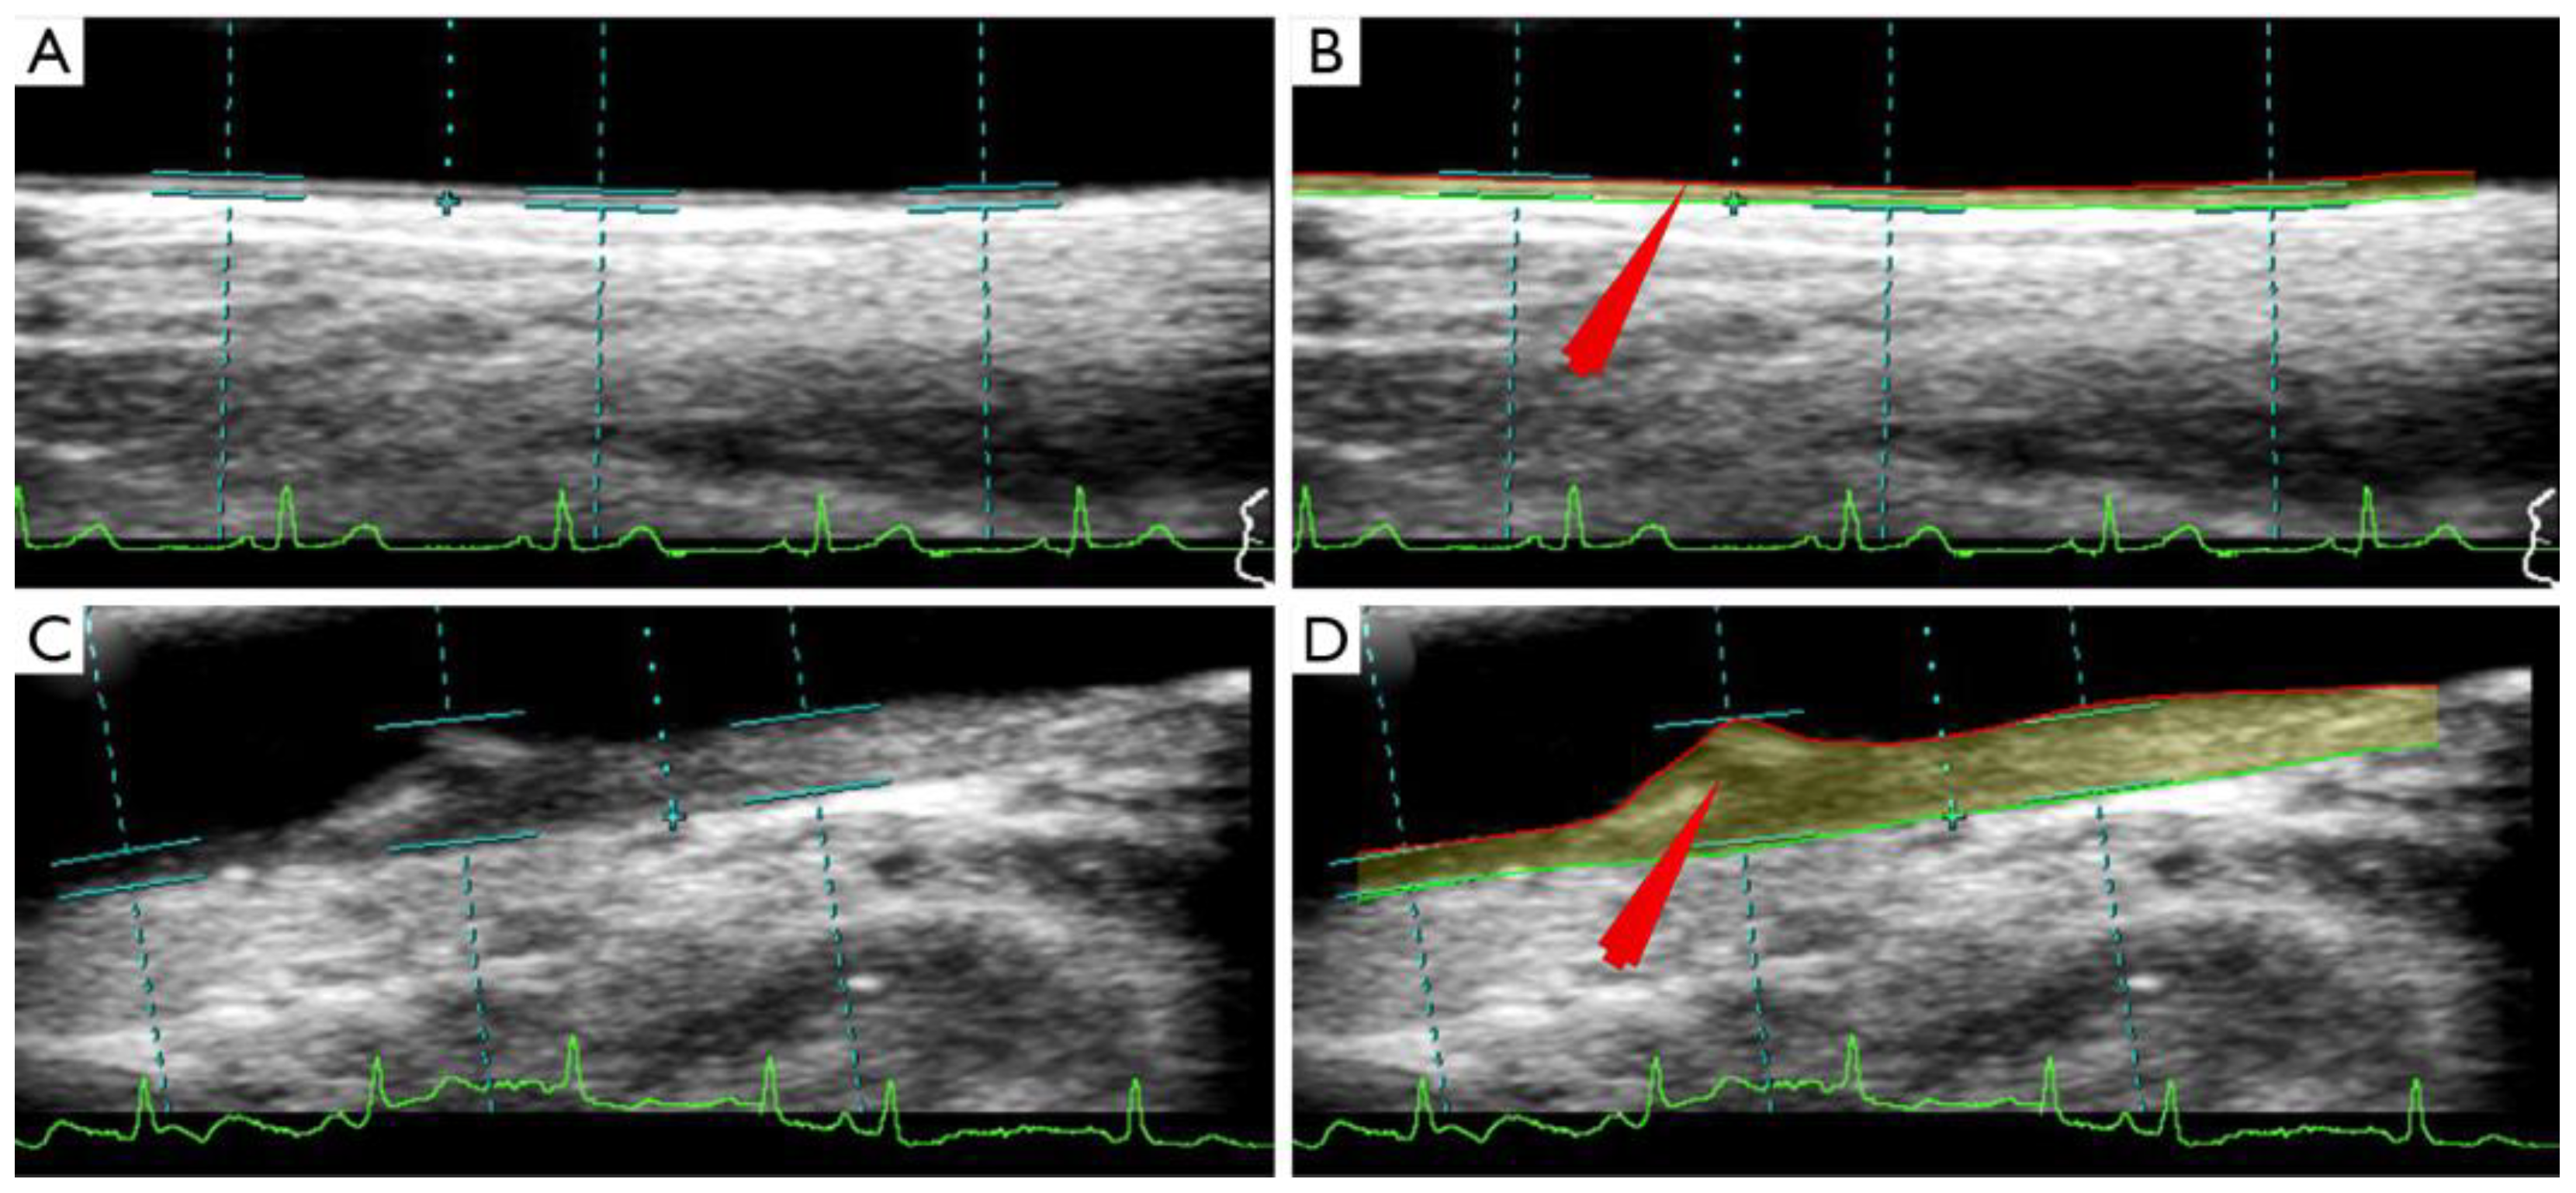

4.2. CUSIP Quantification Using UNet Architectures: UNet, UNet+, UNet++, UNet3P